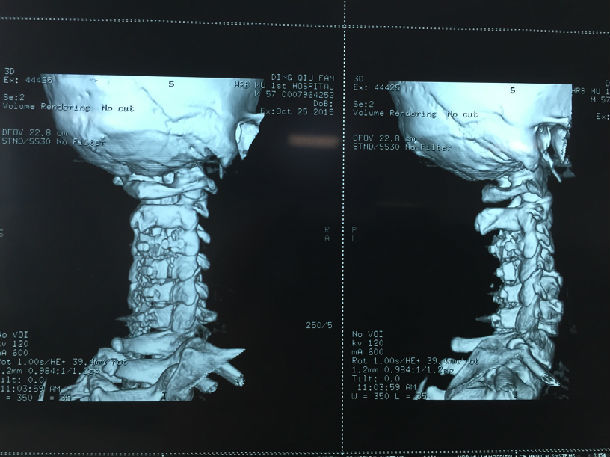

手术前-多节段颈椎间盘突出/黄韧带肥厚/颈椎管狭窄-脊髓损伤

显微镜下经颈后路行单开门椎管扩大成形术-颈椎管明显增宽/脊髓受压解除/患者逐渐康复